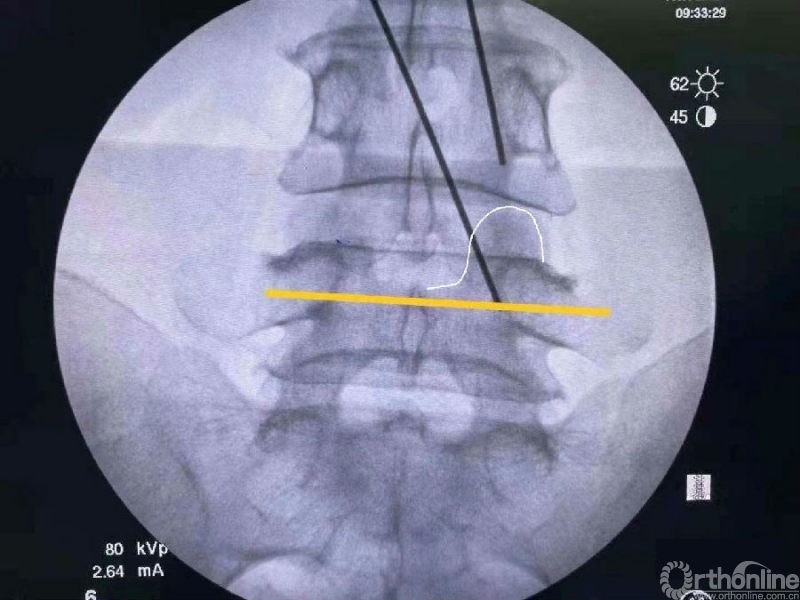

第二次定位虽然并位于椎弓根内缘线上,但是我们觉得本病历参考内缘线的话可能会把下关节突的2/3磨掉,所以我们选择第二个接近椎弓根内缘线的定位孔作为镜下下关节突内缘切除的外界。

术中第一次及第二次的两个定位孔